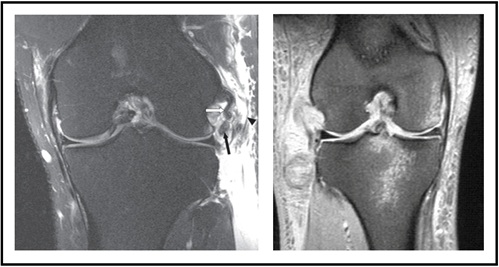

Magnetic Resonance Imaging (MRI) is also routinely ordered to evaluate soft tissue injury to the LCL, popliteus, or biceps tendon (Figure 7-Left). In the sagittal view, fluid may be recognized between the femur and popliteus, indicating that there is a PLC injury. Bone bruising may be seen in an acute setting depending on the mechanism of injury (Figure 7-Right).

Figure 7: MRI depicting PLC Injury)